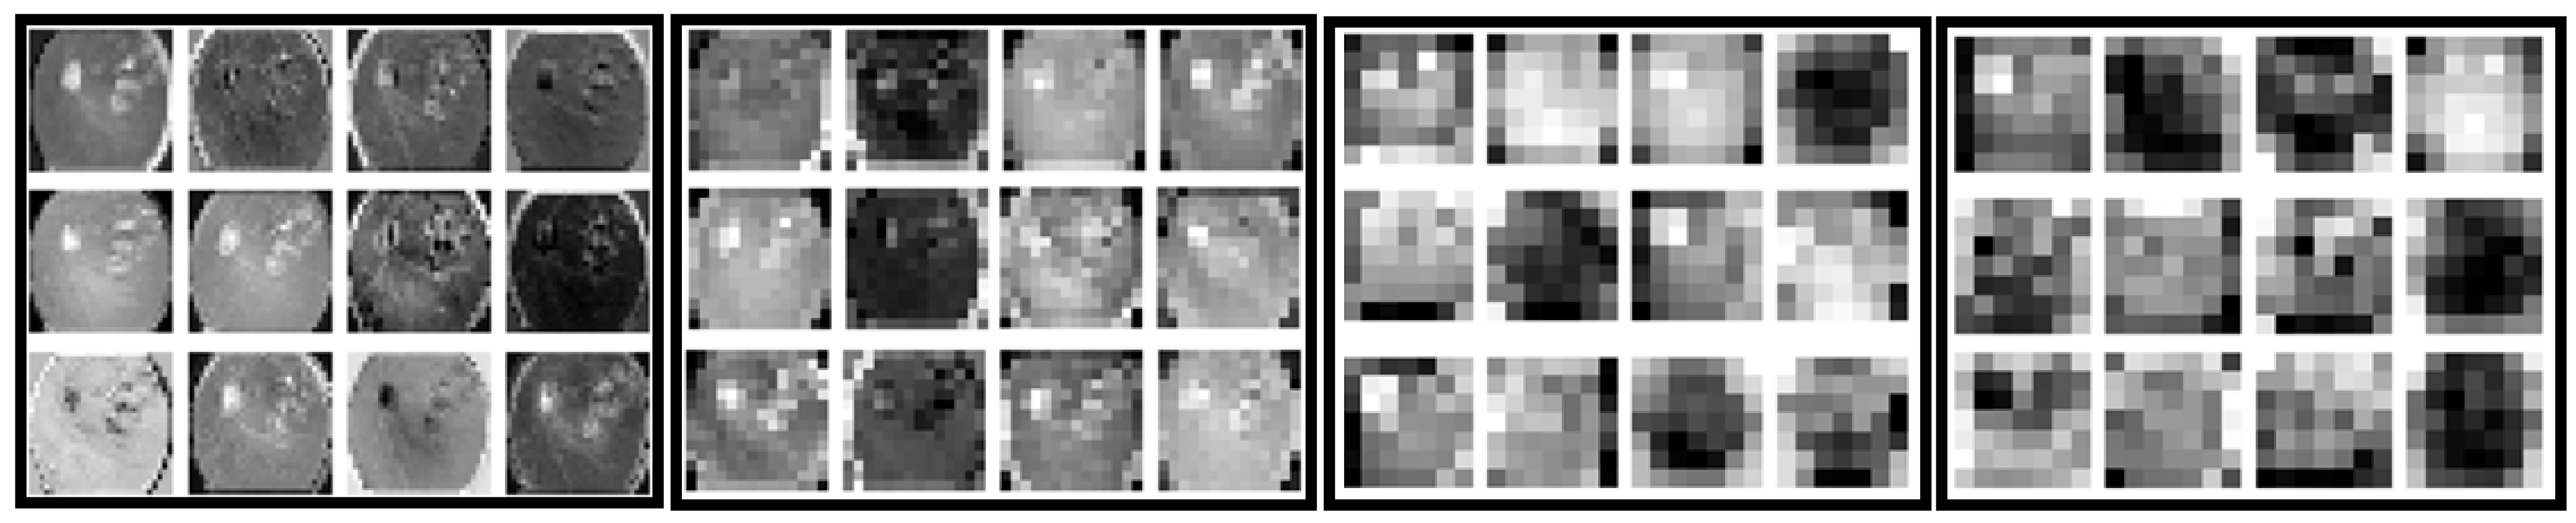

4.4. Grad-CAM-Based Visual Interpretability Analysis of HIRD-Net Predictions